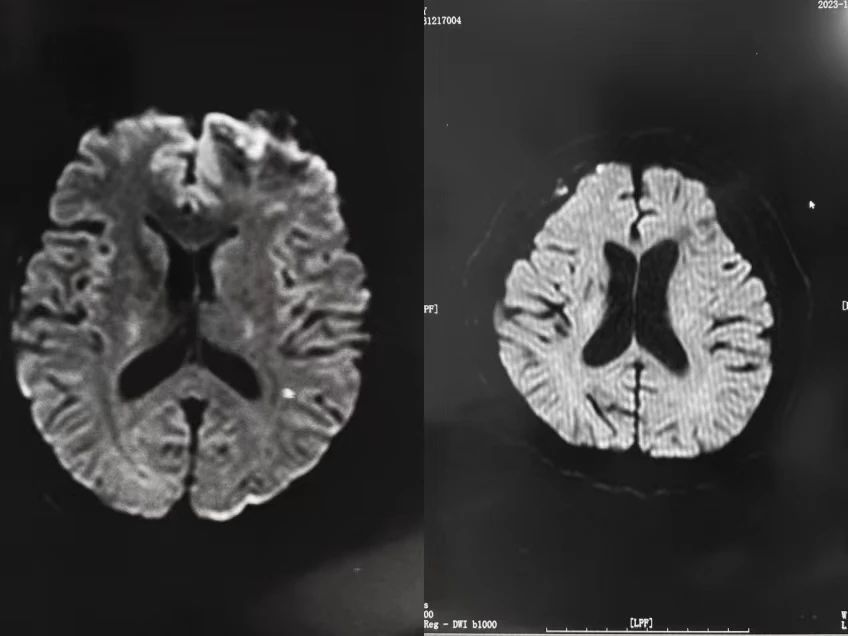

头颅磁共振弥散加权成像即头颅DWI,是功能磁共振的一种,可用于缺血性脑血管病的早期诊断,DWI扫描序列能发现磁共振其他序列无法检出的病灶,还能够对有些病变的鉴别诊断起到决定性的作用。DWI扫描序列在临床中的应用,主要体现在以下几个方面:

一是发现新发脑梗塞,检出新发脑梗塞,是DWI扫描序列应用最为成熟的一个方面,发病半小时就能够发现病灶,2小时肯定能发现病灶,而CT扫描需要24小时才能够发现病灶。

总之,DWI是磁共振临床应用中的一个非常重要的序列,当我们需要发现新发脑梗塞时,就进行DWI扫描;当我们检查脑外伤患者时,需要进行DWI扫描;当我们需要鉴别病变的良恶性时、对表皮样囊肿、脑脓肿等疾病定性诊断时,我们要进行DWI 扫描。